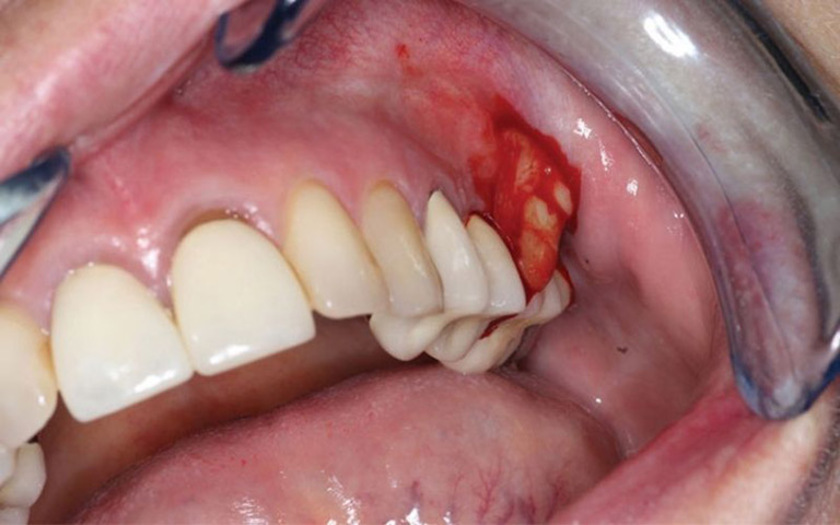

Mọc răng khôn

Đây là tình trạng khá phổ biến ở lứa tuổi trưởng thành khi răng khôn mọc ngầm, mọc lệch gây đau nhức và ảnh hưởng đến các răng bên cạnh. Răng khôn hay răng số 8 là chiếc răng cuối cùng mọc trên cung hàm. Do không đủ chỗ trong cung hàm cho những chiếc răng này mọc nên chúng thường mọc ngầm hoặc không đúng vị trí. Chúng gây ra tình trạng đau âm ỉ kéo dài và lặp đi lặp lại nhiều lần. Răng khôn mọc còn khiến nướu bị sưng tấy, ăn uống khó khăn. Đôi khi còn gây sốt, chán ăn, ảnh hưởng nghiêm trọng đến sinh hoạt hàng ngày.

Răng khôn mọc khiến nướu bị sưng tấy, ăn uống khó khăn